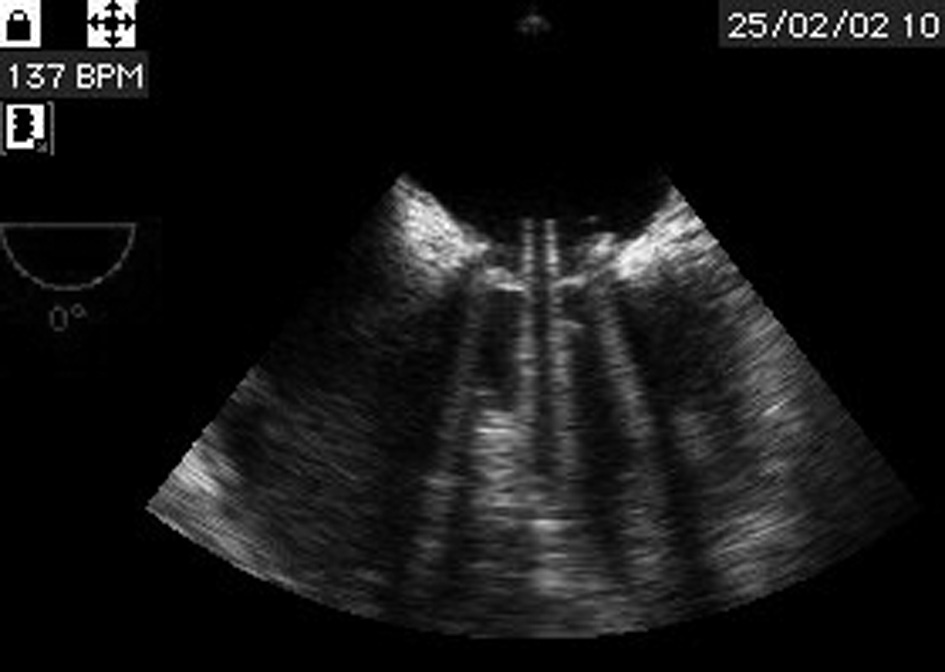

L’ETT et l’ETO sont les examens les plus performants pour la surveillance des prothèses valvulaires et le diagnostic des dysfonctions de prothèse (figure 6).

L’examen bidimensionnel permet d’apprécier le jeu de l’élément mobile.

L’examen au doppler mesure les gradients transprothétiques, surtout le gradient moyen. Couplé à l’examen bidimensionnel, il détermine également la « surface utile » de la prothèse.

Les dopplers continu et couleur permettent également de mettre en évidence une fuite prothétique, intraprothétique ou paraprothétique par désinsertion de la valve.

En cas de suspicion de dysfonction de prothèse, l’ETO est d’un apport essentiel, notamment s’il s’agit d’une prothèse mitrale, qui est particulièrement bien visualisée par cette technique. L’ETO est donc systématique en cas de suspicion de thrombose, d’endocardite sur prothèse ou de désinsertion.